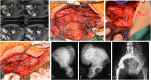

Background: Adequate margins are technically difficult to achieve for malignant tumors involving the sacroiliac joint due to limited accessibility and viewing window. In order to address the technical difficulties faced in iliosacral tumor resection, we proposed a technique for precise osteotomy, which involved the use of canulated screws and Gigli saw (CSGS) that facilitated directional control, anteroposterior linkage of resection points and adequate surgical margins. The purpose of the current study was to evaluate whether CSGS technique facilitated sagittal osteotomy at sacral side, and were adequate surgical margins achieved? Also functional and oncological outcomes was determined along with the noteworthy complications.

Methods: From April 2018 to November 2019, we retrospectively reviewed 15 patients who underwent resections for primary tumors of pelvis or sacrum necessitating iliosacral joint removal using the proposed CSGS technique. Chondrosarcoma was the most common diagnosis. The osteotomy site within sacrum was at ipsilateral ventral sacral foramina in 8 cases, midline of sacrum in 5 cases, and contralateral ventral sacral foramina and sacral ala with 1 case each. The average intraoperative blood loss was 3640 mL (range, 1200 and 6000 mL) with a mean operation duration of 7.4 hours (range, 5 to 12 hours). The mean follow-up was 23.0 months (range, 18 and 39 months) for alive patients.

Results: Surgical margins were wide in 12 patients (80%), wide-contaminated in 1 patient (6.7%), and marginal in 2 patients (13.3%). R0 resection was achieved in 12 (80%) patients and R1 resection in 3 patients. There were three local recurrences (20%) occurred at a mean time of 11 months postoperatively. No local recurrence was observed at sacral osteotomy. The overall one-year and three-year survival rate was 86.7% and 72.7% respectively.Complications occurred in three patients.

Conclusions: The current study demonstrated that CSGS technique for tumor resection within the sacrum and pelvis was feasible and can achieve ideal resection accuracies. The use of CSGS was associated with high likelihood of negative margin resections in the current series. Intraoperative use of CSGS appeared to be technically straightforward and allowed achievement of planned surgical margins. It is worthwhile to consider the use of CSGS technique in resection of pelvic tumors with sacral invasion and iliosacral tumors, however further follow-up at mid to long-term is warranted to observe local recurrence rate.